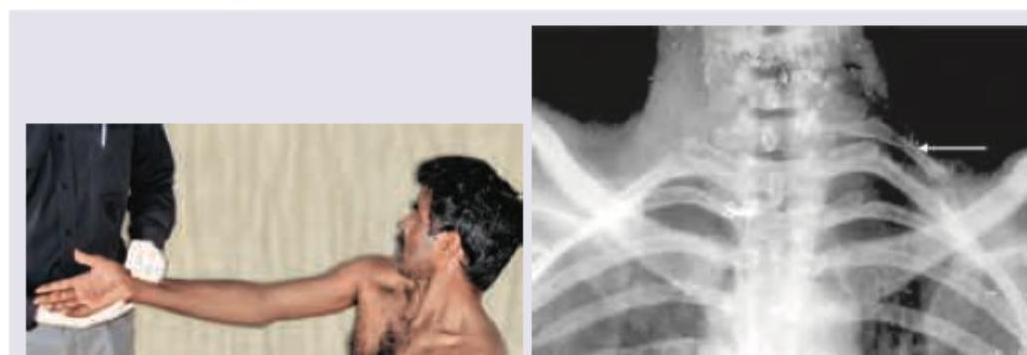

A 40-year-old construction worker presents with pain in the arm on lifting weights. The following test and X-ray of neck was performed. Which is correct about this patient?

Explanation: ***Elevated arm stress test: Cervical rib*** - The image shows a patient performing the **Elevated Arm Stress Test (EAST)**, or Roos Test, which places tension on the neurovascular structures in the thoracic outlet. The X-ray image reveals the presence of a **cervical rib** (indicated by the arrow), a common cause of **thoracic outlet syndrome (TOS)**. - The patient's symptom of **pain in the arm on lifting weights** is consistent with **neurovascular compression** due to a cervical rib, which is often exacerbated by arm elevation. *Adson test: Cervical rib* - The **Adson test** involves palpating the radial pulse while the patient extends, externally rotates the arm, and turns their head toward the ipsilateral arm and inhales. This maneuver compresses the **subclavian artery** by the anterior and middle scalene muscles, not the position shown. - While a cervical rib can cause a positive Adson test, the maneuver depicted in the image is not the Adson test. *Falconer test: Spinal canal stenosis* - The **Falconer test** is not a standard or widely recognized orthopedic special test. - **Spinal canal stenosis** typically presents with different symptoms, such as **neurogenic claudication** or myelopathy, and is assessed with specific neurological examination techniques and imaging (MRI), not the maneuver shown. *Allen test: Fracture of first rib* - The **Allen test** is used to assess **patency of the radial and ulnar arteries** in the hand, and involves compressing both arteries and observing capillary refill. It is not performed as shown in the picture. - A **fracture of the first rib** might cause pain, but the Allen test is not used to diagnose a rib fracture.